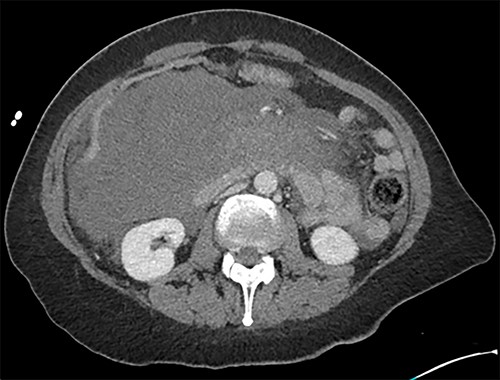

Initially, the main diagnosis considered was an aortic dissection. Other initial general surgical differentials were a perforated viscous or severe pancreatitis. Computed tomography (CT) angiogram showed a 6 mm pseudoaneurysm arising from a branch vessel 3 cm distal to the origin of the SMA. There was no active arterial blush; however, there was a large associated mesenteric haematoma (measuring 4.5 × 8.0 × 13 cm) with large volume haemoperitoneum (Figs 1–3). There was also a splenic artery aneurysm measuring 5 mm with no evidence of active haemorrhage. After the CT scan, she was noted to be haemodynamically unstable when lying supine, due to inferior vena cava compression by the mesenteric haematoma. A pillow was placed under her left lateral side to act as a wedge to reduce this. She proceeded to urgent angioembolization by interventional radiology, which confirmed the pseudoaneurysm on angiography (Fig. 4, left). The SMA was accessed and the aneurysm was successfully embolized with 3 mm diameter 15 cm length Ruby micro-soft detachable coil (Fig. 4, right).

Axial image with arterial phase, demonstrating the pseudoaneurysm arising from a branch of the SMA. There is no active arterial blush.